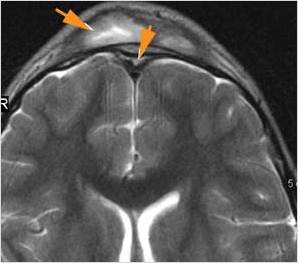

There is brain edema specifically involving the frontal and temporal lobes.

There is cerebritis specifically involving the frontal and temporal lobes.

There is brain abscess specifically involving the frontal and temporal lobes.

There is likely meningitis, meningoencephalitis with complicating hydrocephalus or brain herniation.